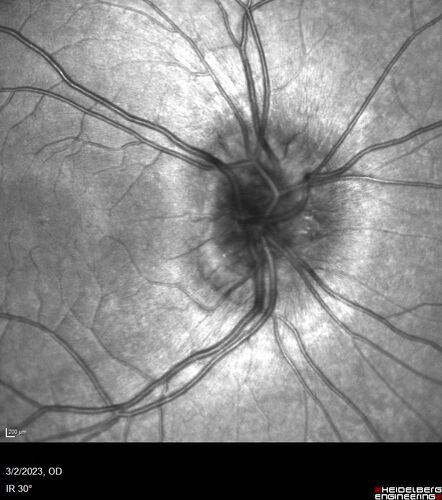

Disc drusen 8 year old boy - fluorescein shows no leakage

8 year old boy with headache and nausea. He had a negative MRI. Images show hyper FAF from drusen and no leakage on FA. No spinal tap was done. VA was 20/40 both eyes.